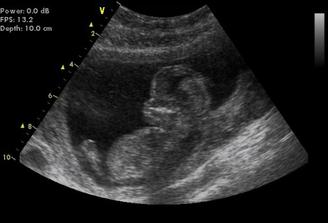

31.12. - velké utz v Gennetu - NT screening (o pár dní dříve nabrána i krev)

Výsledek naprosto v pořádku. Riziko vývojových vad 1:50 000, hodnota NT 1,4, nosní kůstka přítomna 🙂 Odpovídáme 13+4tt, miminko měří 7,5cm a poprvé jsme slyšeli srdíčko 🙂))